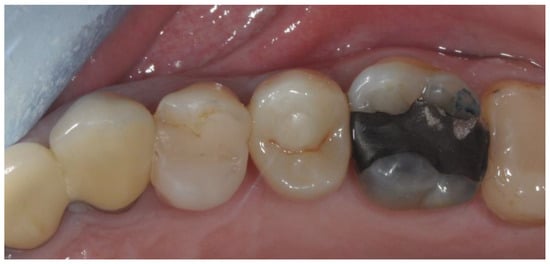

2.3. Prosthetic Protocol